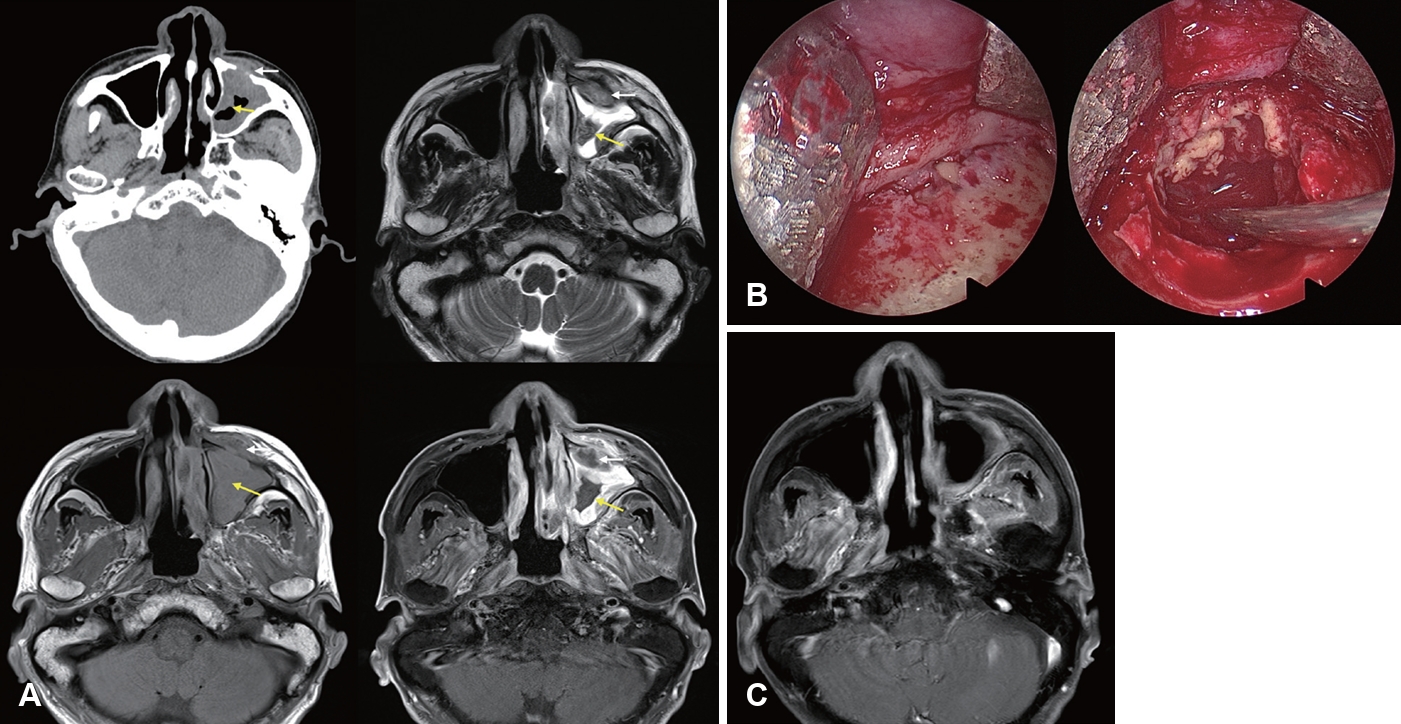

Invasive Fungal Rhinosinusitis: Clinical Features, Imaging Findings, and Treatment Outcomes

Ji Heui Kim

Received June 2, 2025     Accepted July 1, 2025     Published online September 24, 2025

DOI: https://doi.org/10.3342/kjorl-hns.2025.00290

[Epub ahead of print]

kjorl-hns-2025-00290f1.jpgkjorl-hns-2025-00290f2.jpgkjorl-hns-2025-00290f3.jpgkjorl-hns-2025-00290f4.jpgt1-kjorl-hns-2025-00290.png